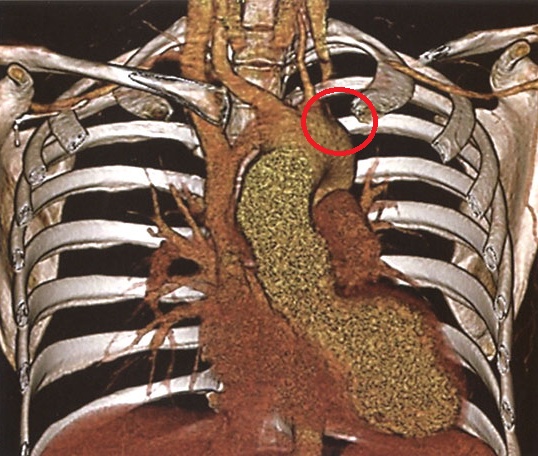

大動脈炎症候群(高安動脈炎、脈なし病)の画像所見は、

罹病期間が長いと動脈壁の石灰化、内腔の狭窄・拡張、動脈瘤を認める

大動脈炎症候群 単純CT (東京レントゲンカンファレンス)